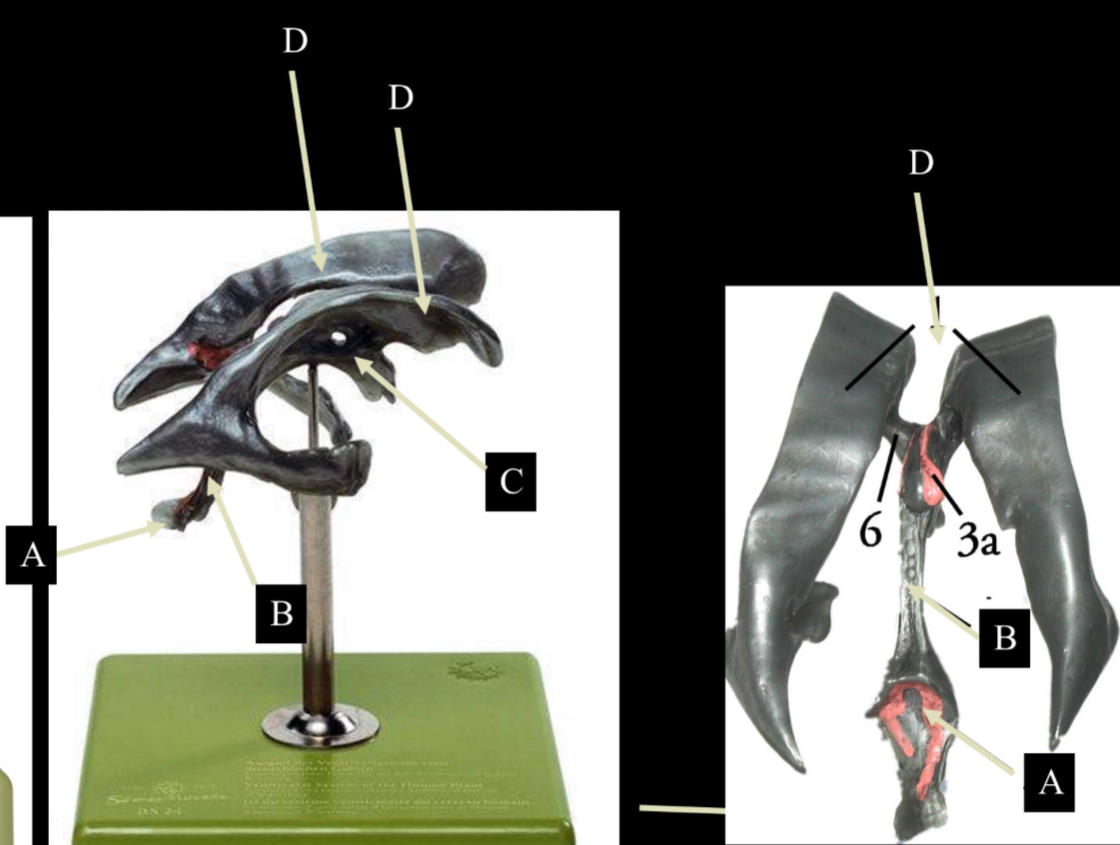

What is D?

lateral ventricle

Imagine thin membrane separating the 2 lateral ventricles

septum pellucidum

What is C?

3rd ventricle

What is B?

cerebral aqueduct

What is A?

4th ventricle

What is below A at the very end?

central canal (spinal cord)